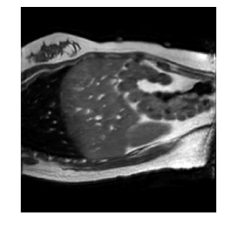

Qualitative results are shown in Fig. 4. We observe no large qualitative differences in the performances of MFIN and MFINc for either loss function. Since, MFINc-SSIM provides the best quantitative results, we show interpolated images from this method and compare them against SCIN-SSIM. Both methods perform well when the motion between the neighbouring images is low. This is reflected in the absence of any structures in the error images in Fig. 4.1. However, RMSE is lower for SCIN because it produces a denoised interpolated image, while MFIN carries over the noise pattern from the neighbouring known image. Whenever there exists high motion between the images being interpolated, SCIN produces blurry images and often misses image structures. This can be observed in cases 2-4 in Fig. 4. For all these cases, MFINc (and also MFIN) produces sharp images and largely preserves structures in the images. Fig. 4.2 shows a case where MFINc additionally has a much better performance with respect to image alignment. Fig. 4.3 shows a representative case, with small improvement in image alignment, yet worse RMSE and SSIM values for MFINc. Finally, Fig. 4.4 shows a case, where MFINc produces worse alignment of structures than SCIN.

Figure 3: Ground truth images (a), SCIN-SSIM results (b) and difference images (c), MFINc-SSIM results (d) and difference images (e). Rows: (1) low motion case, (2)-(4) high motion cases, where MFINc produces (2) much better, (3) slightly better and (4) worse structure alignment that SCIN. (RMSE, SSIM) pairs are indicated over the respective errors images.